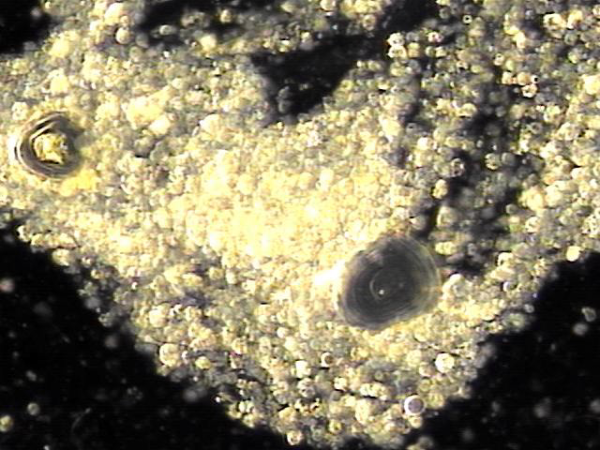

내원 당일 전립선의 표적 치료후 배출된 전립선액의 배양과 PCR 검사를 한후 현미경학적 검사상 치료된 사정관 결석과 전립선의 결석 자료입니다.

On the day of the visit, following targeted prostate treatment, prostatic fluid was discharged and analyzed through culture and PCR testing. Microscopic examination revealed treated ejaculatory duct stones and prostatic calculi.